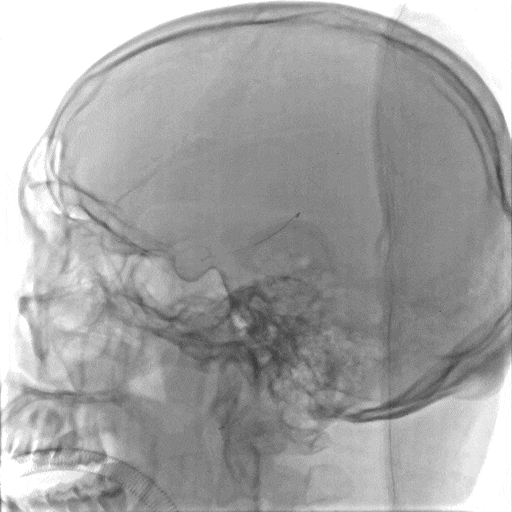

常规消毒、铺巾后,采用改良Seldinger技术穿刺右桡动脉。造影导丝和Sim2造影导管将7F EasyRadial™输送导管置于椎动脉。

正侧位造影提示右侧椎动脉重度狭窄。

200cm微导丝携带微导管路图下穿过狭窄段至左侧大脑后动脉P2段。

沿微导丝送入3.0*15mm 颅内球囊扩张导管至狭窄段给予球囊扩张术。

造影证实狭窄较前明显改善。

沿微导丝送入3.0*12mm 颅内药物洗脱支架至狭窄段。

准确定位后给予球囊扩张、释放支架。

术后造影造影证实支架打开良好,贴壁良好,无残余狭窄,远端未见明显栓塞表现。